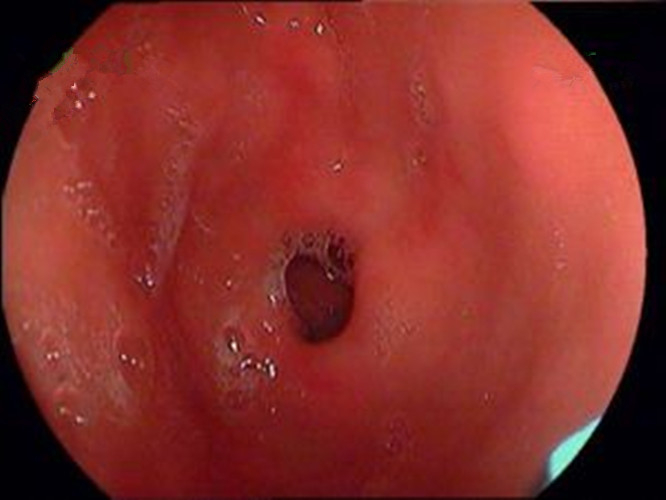

萎縮淺表性慢性胃炎